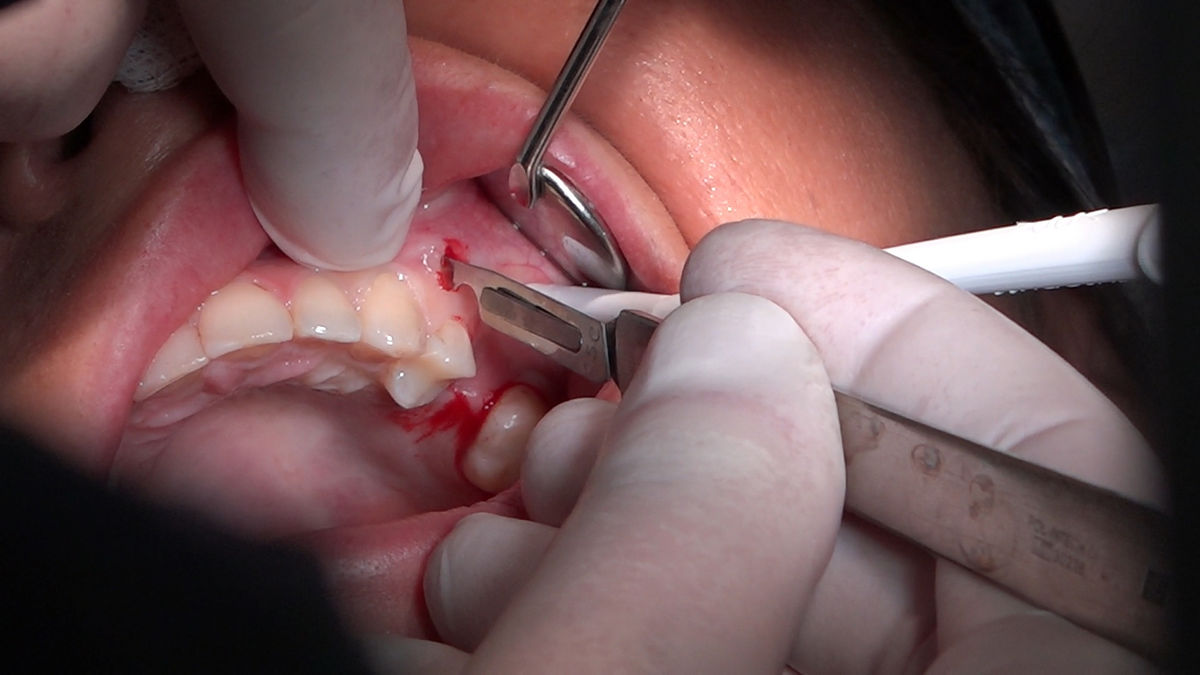

Chirurgia implantologiczna to temat wiodący 5 Sesji X Sezonu Practiculum Implantologii, która się odbyła 23-24 października 2020 roku. Bierze w nim udział 16 adeptów implantologii stomatologicznej. Zabiegi z udziałem Pacjentów jak zwykle poprzedziło omówienie i planowanie, tym bardziej, że zgodnie z planem wykonana została implantacja z wykorzystaniem szablonu chirurgicznego, który przygotowało laboratorium dentystyczne Wiligała Lab. Kursanci wykonywali szereg zabiegów implantologicznych i chirurgicznych oraz regeneracyjnych z zastosowaniem PRF, w tym sinus lift. Przeprowadzali je pod kierunkiem Lidera Umiejętności Implantologicznych dr n.med. Violetty Szycik, która wysoko oceniła wykonanie zabiegów.